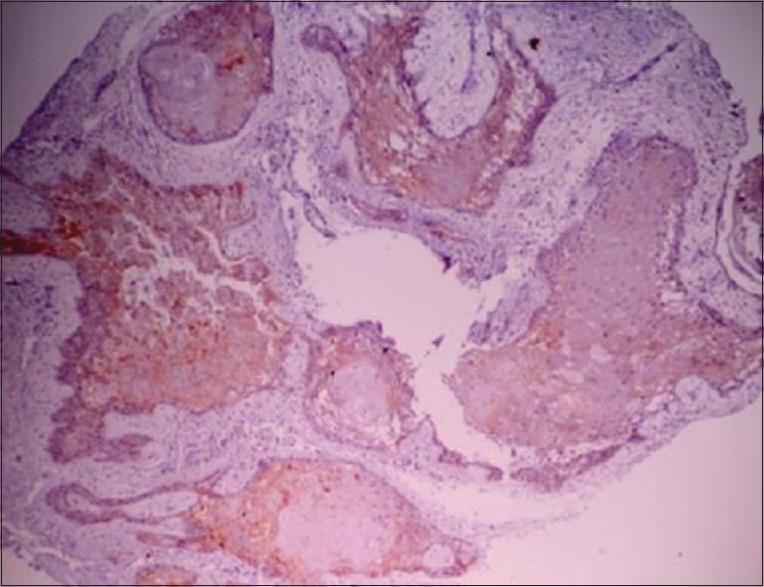

A total of eighty cases, in which twenty cases each of ameloblastoma, unicystic ameloblastoma, dentigerous cyst, and odontogenic keratocyst (OKC) were included in the study. Slides were made from the archival blocks of each case and were stained immunohistochemically with calretinin.

Correlation between calretinin staining and histopathological diagnosis was done, and it was found that all twenty cases of ameloblastoma showed positivity for calretinin, whereas 17 of twenty cases of unicystic ameloblastoma showed positivity for calretinin staining. All the cases of OKC and dentigerous cyst were negative for calretinin.

对钙视网膜蛋白染色与组织病理学诊断之间进行相关性分析,发现所有20例成釉细胞瘤病例钙视网膜蛋白呈阳性,而20例单囊性成釉细胞瘤病例中有17例钙视网膜蛋白染色呈阳性。所有OKC和含牙囊肿病例钙视网膜蛋白均为阴性。